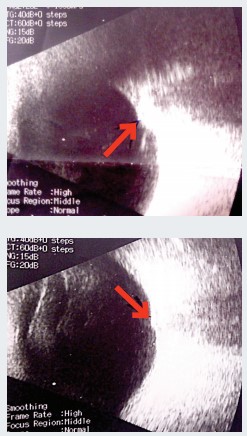

Рисунок 1. Эхоскопия. Стрелка указывает на ДЗН, проминирующий в стекловидное телоЭхоскопия. ОD — умеренная деструкция стекловидного тела, задняя гиалоидная мембрана (ЗГМ) частично отслоена, оболочки прилежат, в ДЗН гиперэхогенное включение (друзы?). OS — умеренная деструкция стекловидного тела, ЗГМ частично отслоена, оболочки прилежат, в ДЗН гиперэхогенное включение, ДЗН проминирует в стекловидное тело (см. рис. 1).

Осмотр глазного дна с фундус-линзой. OS — в основании ДЗН округлое проминирующее пигментированное (меланоцитома?) образование, границы и ткань ДЗН не определяются, мелкая капиллярная сеть по поверхности ДЗН, гиперпапиллярно отек нейроэпителия сетчатки (НЭС). Окклюзия артерий по верхневисочной и носовой аркадам, в зоне верхневисочной и верхненосовой аркад молочно-белый отек сетчатки с захватом верхней части фовеа. Сетчатка прилежит (см. рис. 2). Лазерная коагуляция не показана. Рекомендована консультация онкоофтальмолога.